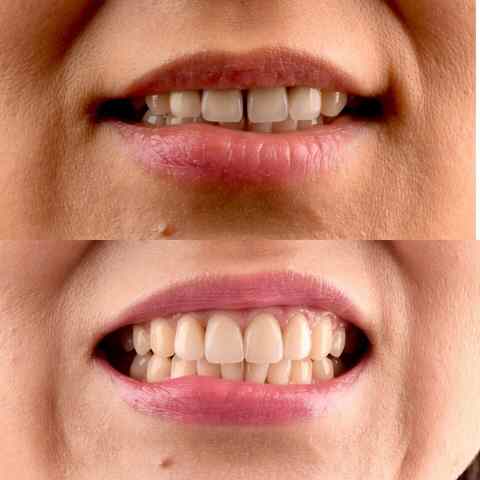

- Реставрация зубов.

- Клиническое отбеливание зубов.

Стоматологический центр Whitestory (Уайтстори): Мы воссоздаем естественную красоту.

Примеры работ